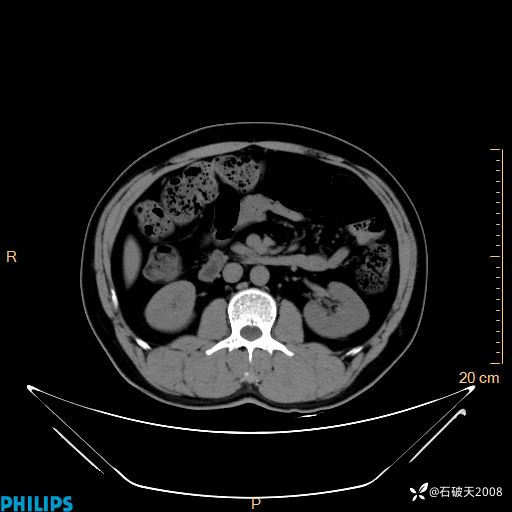

平扫轴位